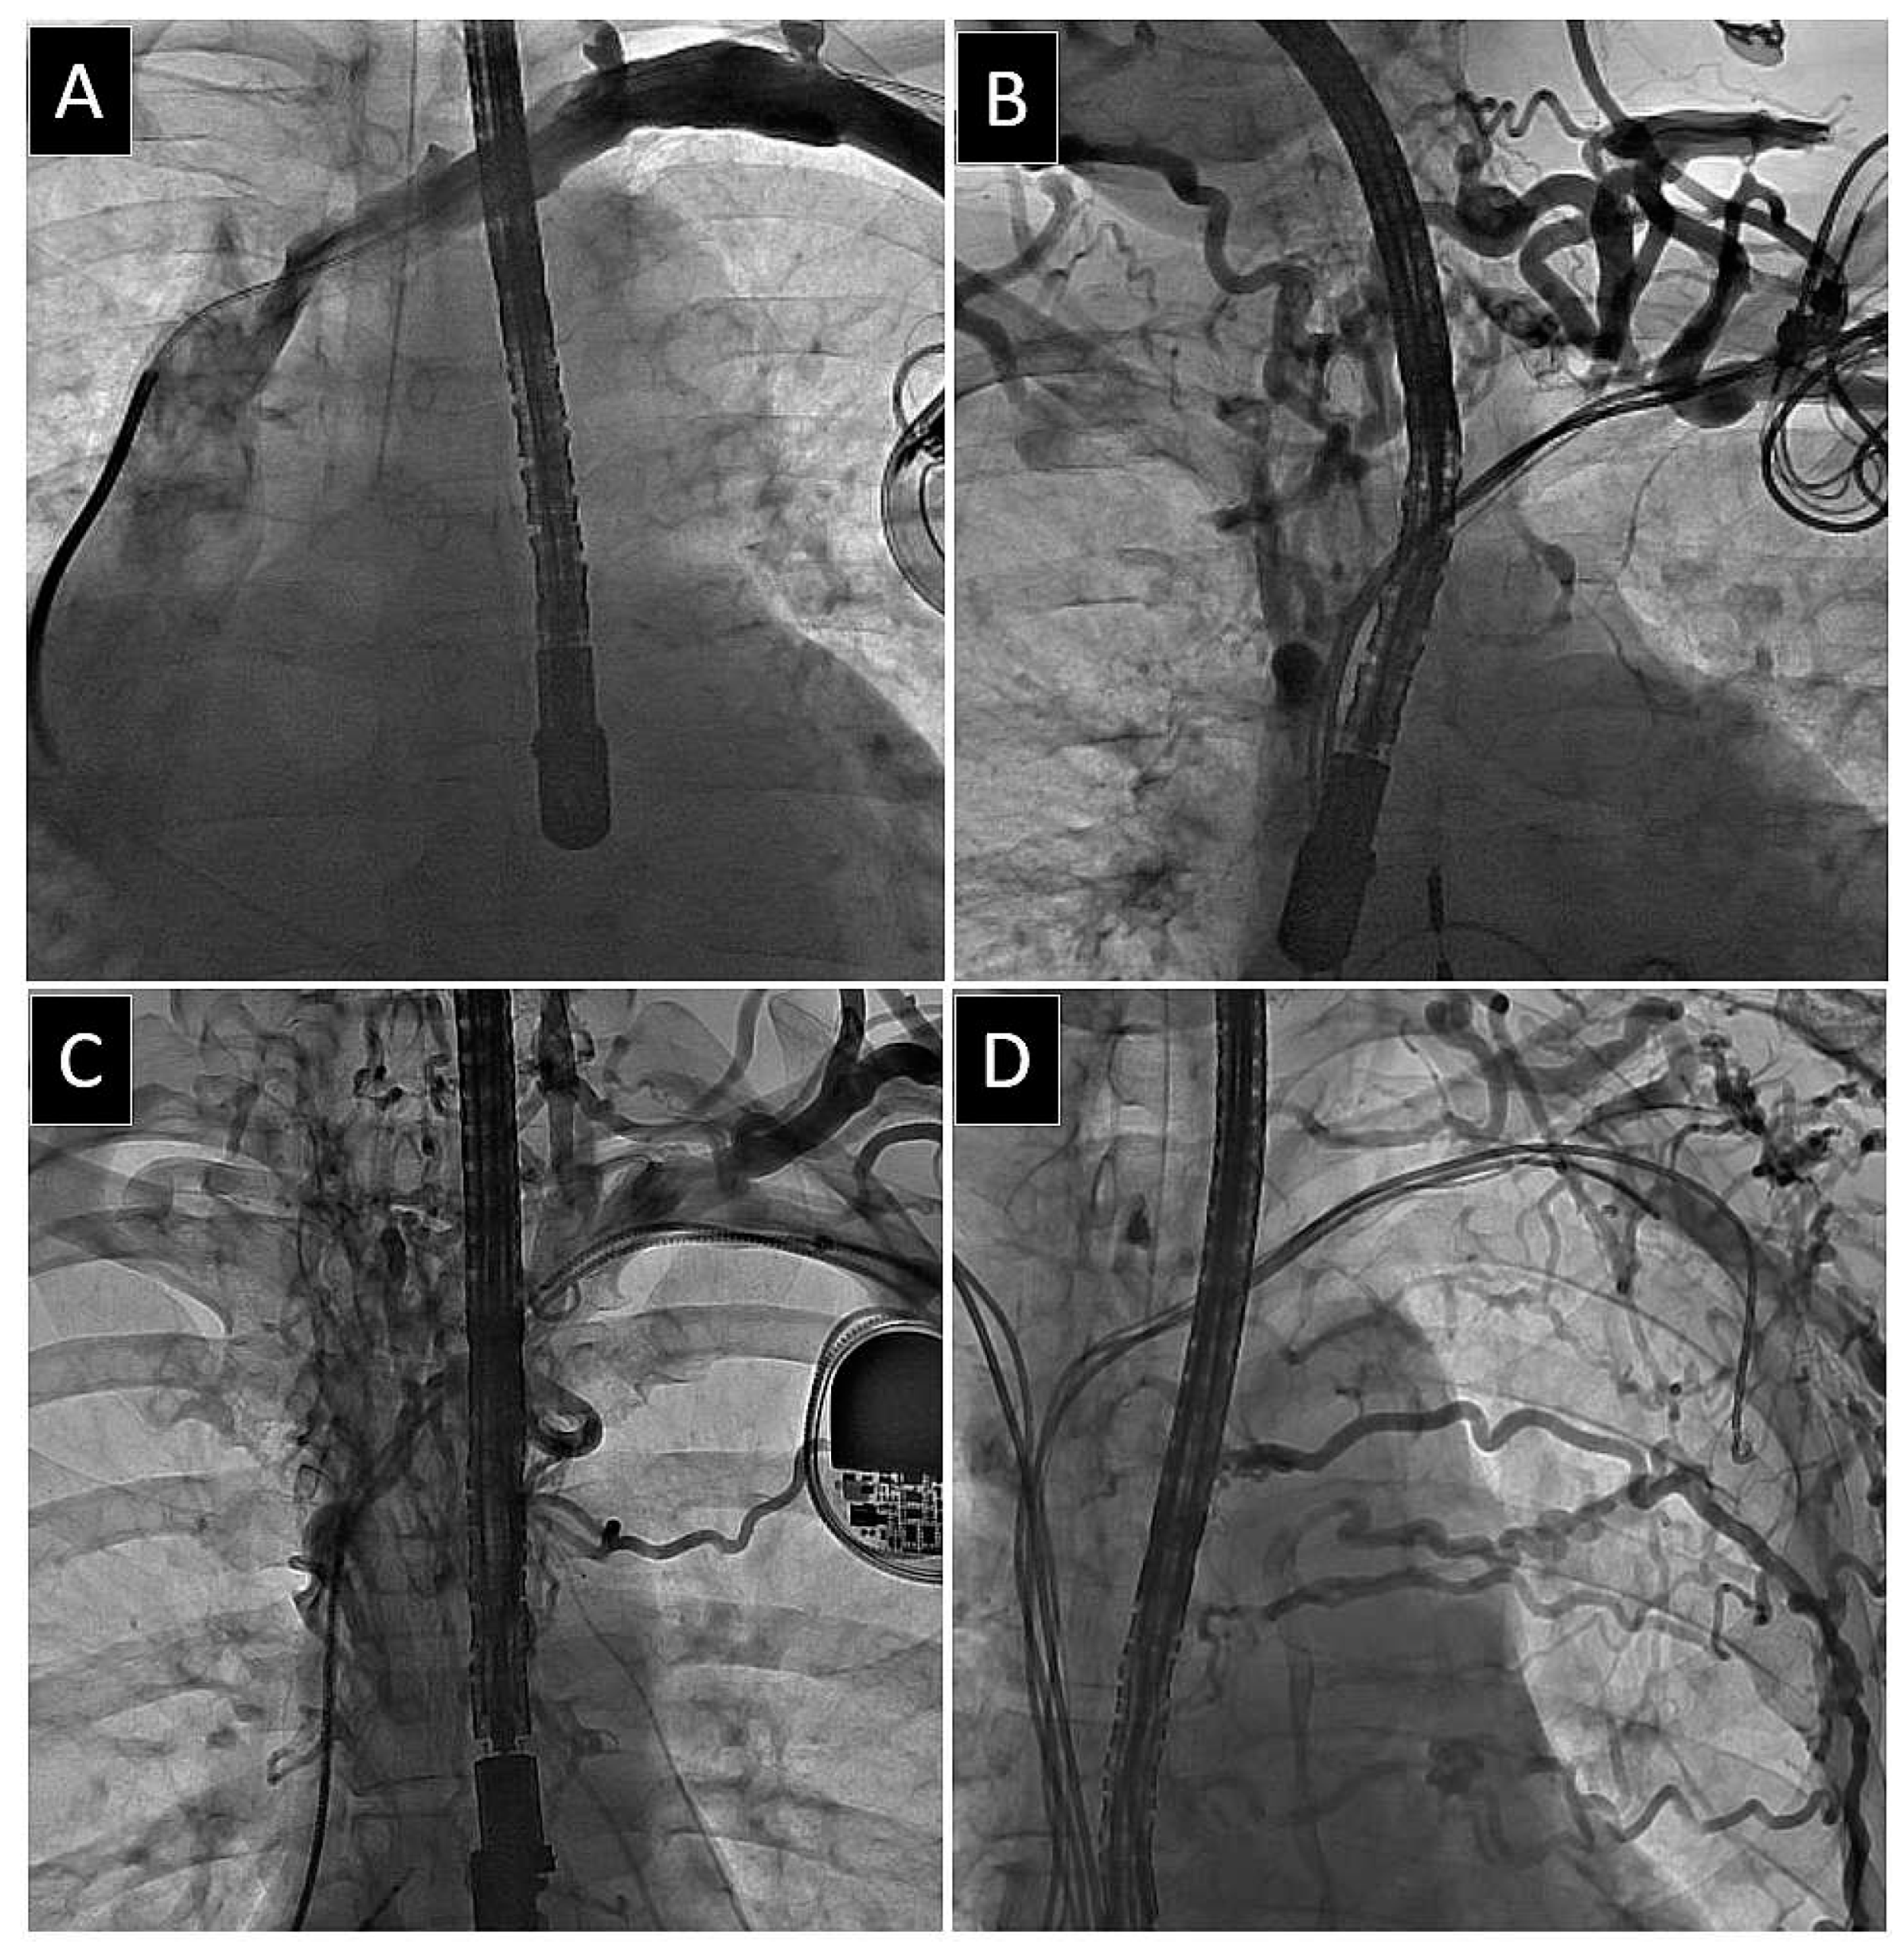

| Any Level of LRVSO | Two-Level Nature of LRVSO | Three- or More Level Nature of LRVSO | |||||||||||||

|---|---|---|---|---|---|---|---|---|---|---|---|---|---|---|---|

| Univariable Regression | Multivariable Regression | Univariable Regression | Multivariable Regression | Univariable Regression | Multivariable Regression | ||||||||||

| OR | p | OR | 95%CI | p | OR | p | OR | 95%CI | p | OR | p | OR | 95%CI | p | |

| Patient’s age during first system implantation [years] | 1.007 | 0.003 | 1.005 | 0.999 −1.012 | 0.115 | 1.011 | <0.001 | 1.015 | 1.007 −1.024 | <0.001 | 1.005 | 0.580 | |||

| Patient’s age during TLE [years] | 1.009 | 0.002 | 1.016 | <0.001 | 0.993 | 0.352 | |||||||||

| Baseline heart disease: post-inflammatory, congenital, channelopathies, neurocardiogenic, or unknown | 1.015 | 0.768 | 0.929 | 0.527 | 2.634 | <0.001 | 1.358 | 0.735 −2.507 | 0.328 | ||||||

| RV diameter | 0.977 | <0.001 | 0.980 | 0.966 −0.993 | 0.004 | 0.980 | 0.018 | 0.991 | 0.972 −1.010 | 0.344 | 0.971 | 0.183 | |||

| AF permanent | 0.749 | 0.001 | 0.702 | 0.570 −0.865 | 0.001 | 0.620 | <0.001 | 0.548 | 0.415 −0.723 | <0.001 | 0.493 | 0.034 | 0.537 | 0.251 −1.152 | 0.110 |

| Arterial hypertension | 1.224 | 0.009 | 1.121 | 0.936 −1.342 | 0.213 | 1.267 | 0.015 | 1.165 | 0.924 −1.468 | 0.196 | 0.875 | 0.574 | |||

| Body mass index | 0.988 | 0.146 | 0.977 | 0.033 | 0.972 | 0.949 −0.995 | 0.019 | 0.871 | <0.001 | 0.864 | 0.808 −0.925 | <0.001 | |||

| Charlson’s index | 1.013 | 0.210 | 1.020 | 0.136 | 0.958 | 0.227 | |||||||||

| Device type—CRT-D | 1.543 | 0.004 | 0.762 | 0.499 −1.163 | 0.208 | 1.861 | <0.001 | 0.695 | 0.418 −1.154 | 0.159 | 0.672 | 0.512 | |||

| Number of leads in the system before TLE | 1.518 | <0.001 | 1.890 | <0.001 | 1.409 | 0.071 | |||||||||

| Presence of abandoned lead before TLE | 1.661 | <0.001 | 2.706 | <0.001 | 7.139 | <0.001 | |||||||||

| Number of abandoned leads before TLE | 1.459 | <0.001 | 2.058 | <0.001 | 3.642 | <0.001 | |||||||||

| Multiple abandoned leads before TLE | 1.916 | 0.012 | 3.314 | <0.001 | 10.46 | <0.001 | |||||||||

| Number of leads in the heart before TLE | 1.532 | <0.001 | 1.332 | 1.111 −1.596 | 0.002 | 2.004 | <0.001 | 1.706 | 1.366 −2.132 | <0.001 | 2.531 | <0.001 | 1.688 | 1.081 −2.635 | 0.021 |

| ≥ 4 leads before TLE | 2.692 | 0.001 | 5.232 | 2.910 | 14.01 | <0.001 | |||||||||

| ≥ 5 leads before TLE | 10.69 | <0.001 | 10.69 | 0.027 | 46.48 | <0.001 | |||||||||

| ICD leads—before TLE | 0.991 | 0.172 | 0.990 | 0.292 | 0.467 | 0.018 | 0.543 | 0.256 −1.153 | 0.111 | ||||||

| CS lead presence before TLE (for LA or LV pacing) | 1.341 | <0.001 | 1.247 | 1.047 −1.485 | 0.013 | 1.491 | <0.001 | 1.274 | 1.028 −1.578 | 0.027 | 1.170 | 0.391 | |||

| Leads both side of the chest before TLE | 1.700 | 0.043 | 1.015 | 0.520 −1.981 | 0.965 | 3.230 | <0.001 | 1.513 | 0.791 −2.896 | 0.211 | 18.67 | <0.001 | 7.203 | 2.716 −19.10 | <0.001 |

| Upgrading or additional lead implantation | 1.395 | 0.004 | 0.815 | 0.591 −1.125 | 0.213 | 1.964 | <0.001 | 0.917 | 0.628 −1.339 | 0.653 | 2.747 | <0.001 | 0.648 | 0.188 −2.237 | 0.492 |

| Upgrading or downgrading with lead abandonment | 2.373 | <0.001 | 2.488 | 1.483 −4.174 | 0.001 | 3.705 | <0.001 | 2.286 | 1.269 −4.119 | 0.006 | 7.731 | <0.001 | 2.789 | 0.618 −12.59 | 0.182 |

| Dwell time of the oldest lead before TLE | 1.003 | 0.593 | 1.013 | 0.099 | 1.061 | <0.001 | |||||||||

| Cumulative dwell time of leads (in years) before TLE | 1.007 | 0.016 | 0.998 | 0.990 −1.007 | 0.714 | 1.016 | <0.001 | 0.996 | 0.986 −1.005 | 0.345 | 1.036 | <0.001 | 0.992 | 0.973 −1.011 | 0.416 |

| Strong connective tissue scar connection of the lead with heart structures (any) | 0.744 | 0.014 | 0.649 | 0.873 | 0.708 | 0.400 | |||||||||

| Strong connective tissue scar connection of the lead with RA wall | 0.568 | 0.006 | 0.603 | 0.395 −0.920 | 0.019 | 0.669 | 0.125 | 0.880 | 0.835 | ||||||

| TV regurgitation [grades I and II] | 1.066 | 0.502 | 0.916 | 0.475 | 0.548 | 0.025 | 0.583 | 0.301 −1.127 | 0.108 | ||||||